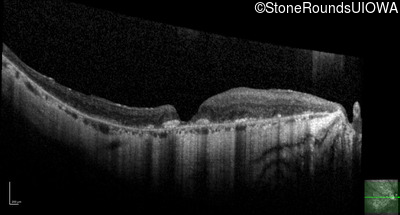

Optical Coherence Tomography - Left - 20/80 -1

Exemplar / OCT Stack